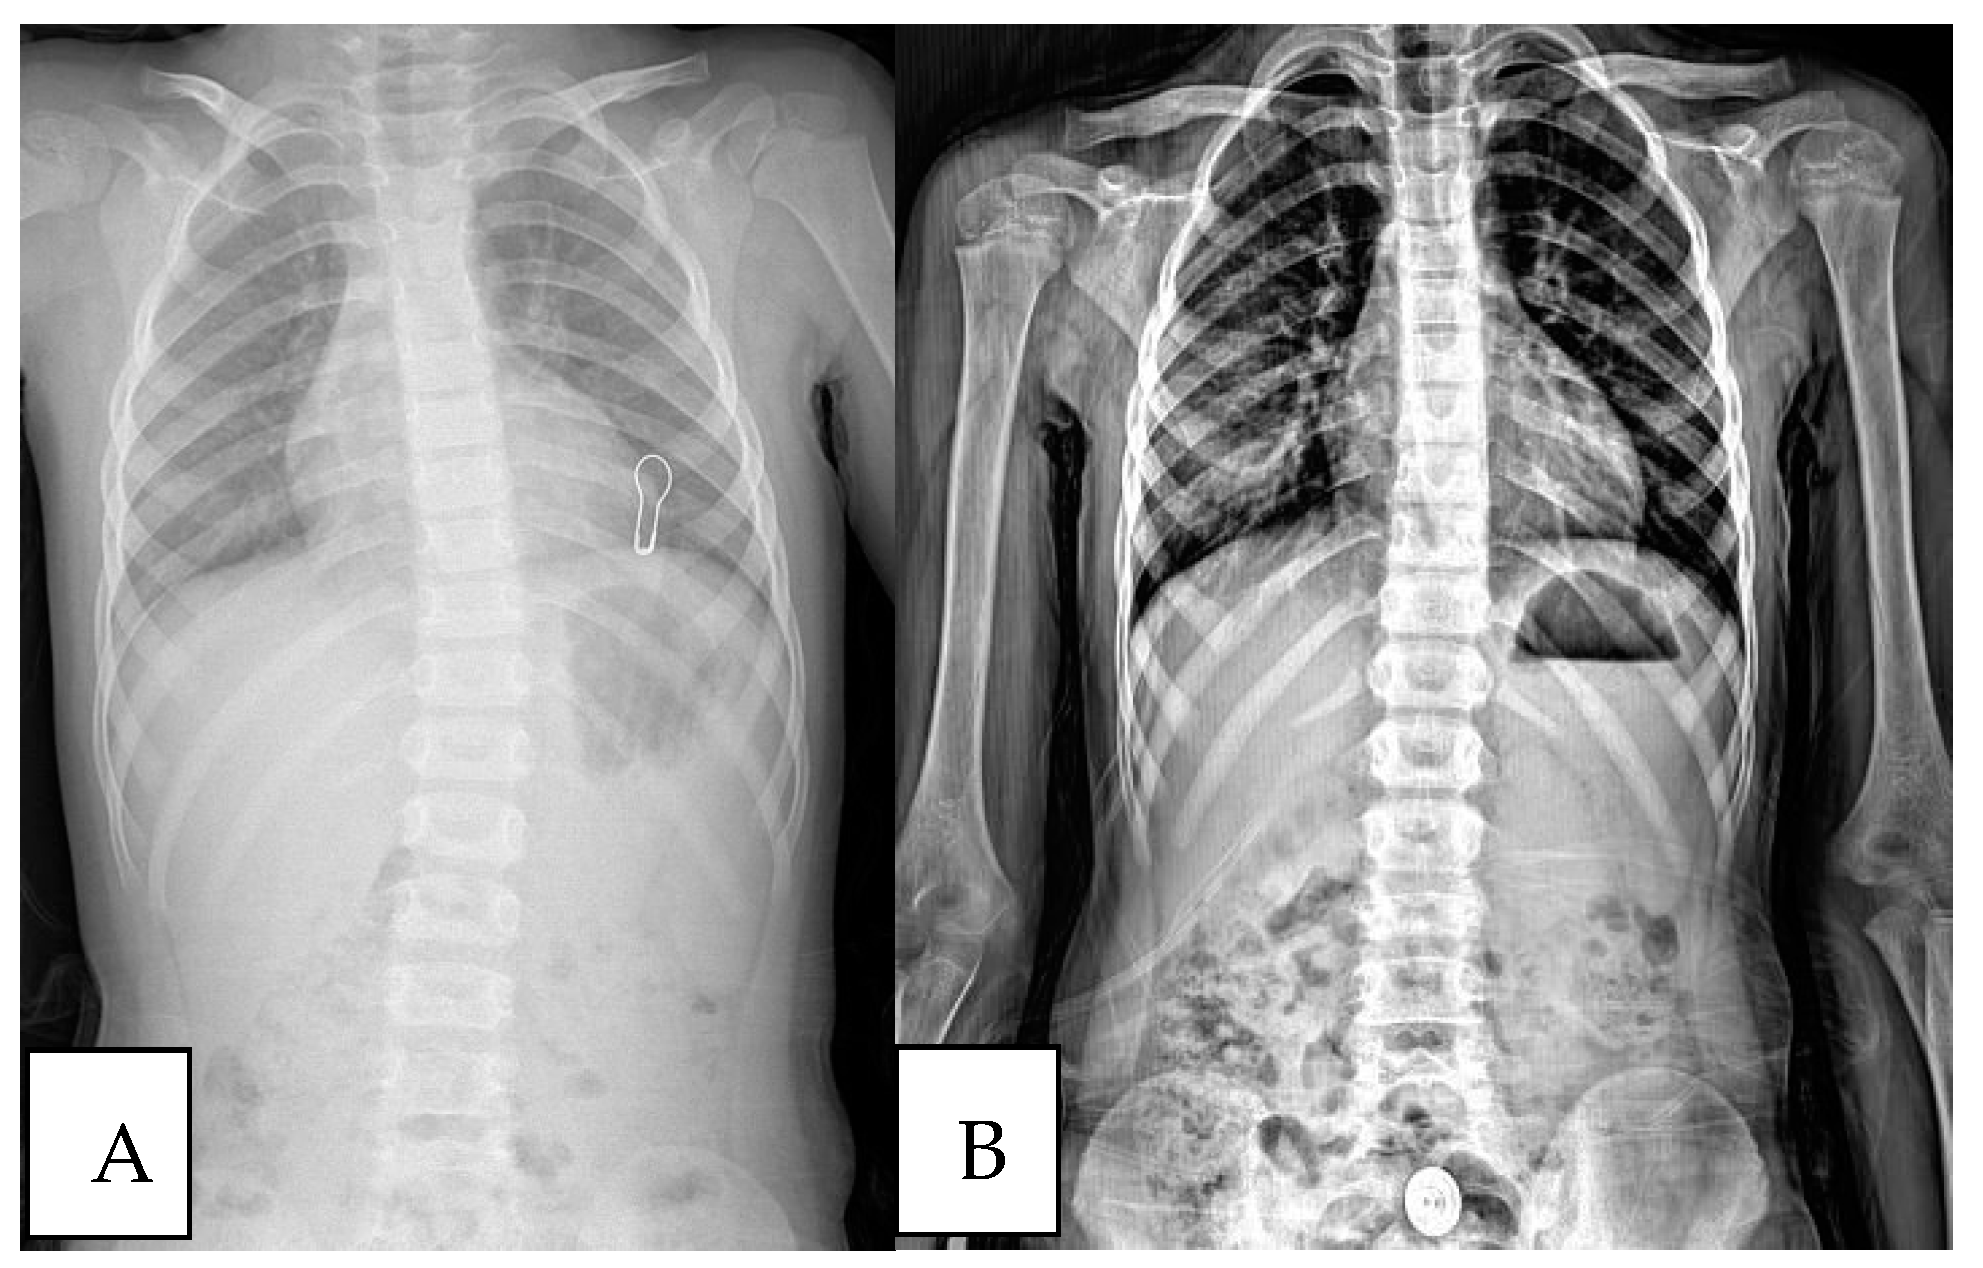

- Pan, X.-X.; Huang, C.-A.; Lin, J.-L.; Zhang, Z.-J.; Shi, Y.-F.; Chen, B.-D.; Zhang, H.-W.; Dai, Z.-Y.; Yu, X.-P.; Wang, X.-Y. Prevalence of the Thoracic Scoliosis in Children and Adolescents Candidates for Strabismus Surgery: Results from a 1935-Patient Cross-Sectional Study in China. Eur. Spine J. 2020, 29, 786–793. [Google Scholar] [CrossRef]

- Kockara, N.; Ucpunar, H. The Value of Standard Chest Radiography in the Diagnosis of Scoliosis. Ann. Med. Res. 2019, 26, 190–193. [Google Scholar] [CrossRef]

- Oh, C.H.; Kim, C.G.; Lee, M.S.; Yoon, S.H.; Park, H.-C.; Park, C.O. Usefulness of Chest Radiographs for Scoliosis Screening: A Comparison with Thoraco-Lumbar Standing Radiographs. Yonsei Med. J. 2012, 53, 1183. [Google Scholar] [CrossRef]